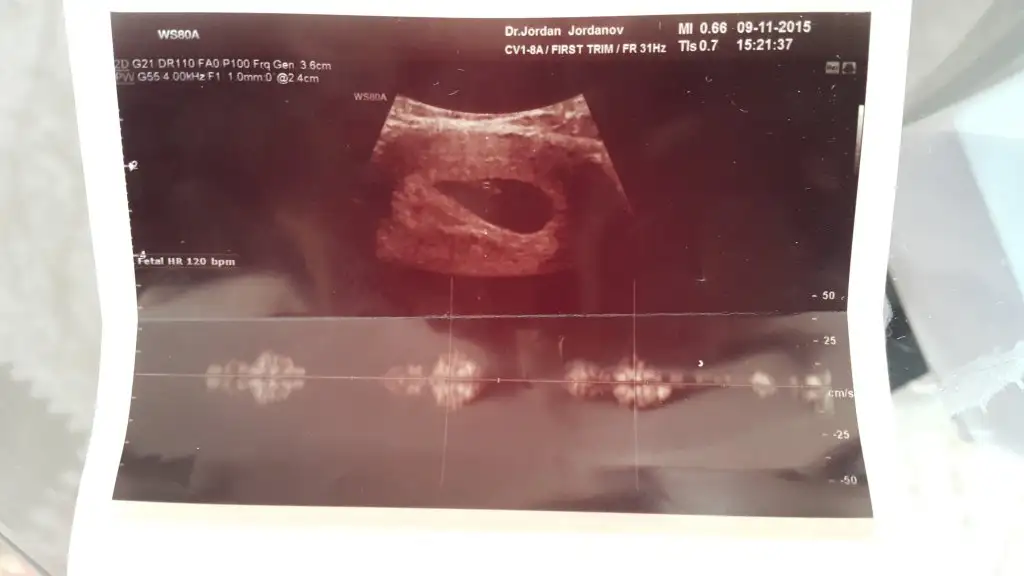

Doktor bana 6 haftalıksın demişti.

Kese 6 hafta icin bana büyük geldi.

Internete bakıyorum bebeklerde daha buyuk keselerde daha kucuk oluyor.

Bende tam tersi bebek cok kucuk gozukuyor kese buyuk sanki

Canım doktor fotoğrafı nasıl kaydettiyse öyle çıkıyor.. yakınlaştırıyor.. uzaklaştırıyor..

canim gunaydin doktor hersey yolunda diyosa tamamdir ben gebeligimi ögrendigimden beri cok huzursuzdum. ilk olarak adet sonrasi milletin beta hcgsi 500-700 falandi benimki 100 cok korkuyordum.. sonra kese görulmedi benden sonra olanlar bile görmustu..nihayet kese göruldu ici bostu.. bekledim bekledim sonra kalp atisi icin gittik.. hep kiyaslamalar yaptim benden sonra gördu ben niye göremedim vs diye. benim kese 8 mm baskalarininki iki katiydi.. doktor bana göre 7 haftalikken gittigimde 5-6 haftalik dedi eyvah geriden geliyorum dedim:) iki hafta sonra haftasina uyumluydu.. demem o ki biz nekadsr kese boyutuna mm cm kafamiza yorsakta bebeklerimiz masallah cok hizli buyuyor ve sonraki haftalarda toparliyo.. belki iki hafta sonra gittiginde önde olacaksin hic belli olmuyor.. bunlari dusunup yorma kendini inan bana sadece kendini uzuyosun...